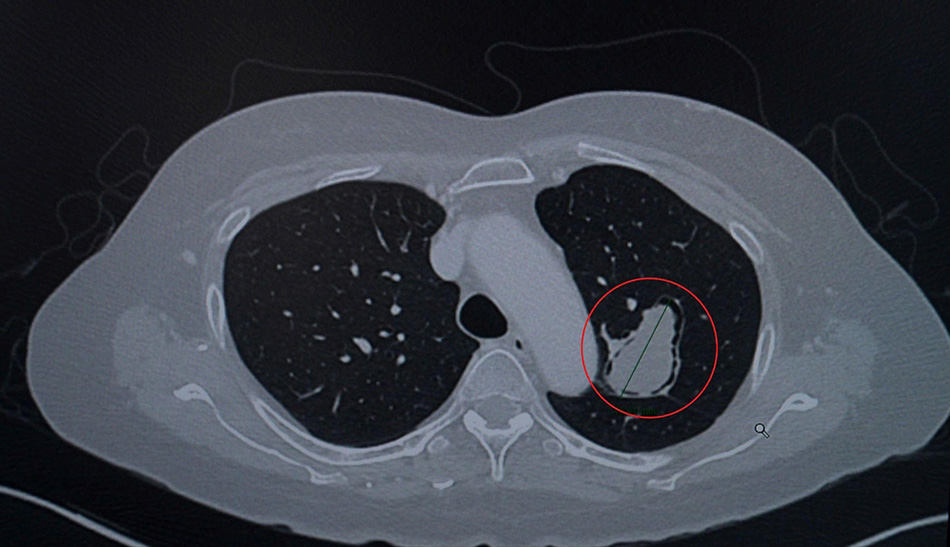

Hình ảnh CT ngực cho thấy khối u nấm phổi (khoanh đỏ) nằm ở thùy trên phổi trái, sát đường thở và động mạch chủ ngực với đường kính hơn 4cm. (Ảnh:FV)

Bà L. sau đó sang Việt Nam và đến khám tại Bệnh viện FV. ThS.BS.CKII Lương Ngọc Trung –Trưởng khoa Mạch máu & Can thiệp nội mạch, chuyên gia phẫu thuật lồng ngực – nhận định tình trạng của bệnh nhân giống như một “quả bom hẹn giờ”. Khối u nấm có kích thước lên đến 4,6cm, nằm sát đường thở và động mạch chủ , tiềm ẩn nguy cơ xâm lấn mạch máu hoặc vỡ vào đường hô hấp.